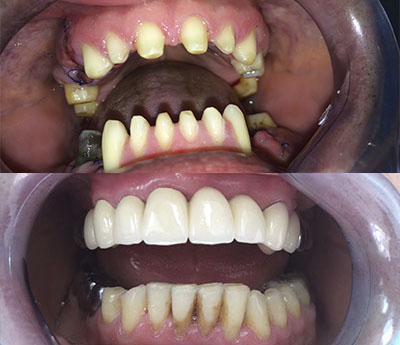

Un tale pezzo protesico ripristina l'integrità delle arcate dentarie. Una protesi mobile correttamente realizzata migliorerà esteticamente i lineamenti del viso del paziente, consentirà il ripristino della funzione masticatoria e migliorerà la fonazione.

Oltre al ripristino estetico della dentatura, il ponte dentale previene le complicazioni che possono derivare dalla mancanza di un dente. Una volta applicato, completerà il normale processo di masticazione e migliorerà la funzione fonetica.

Il sistema Fast&Fixed è un'alternativa immediata. Questa procedura ti permetterà di ritrovare il tuo sorriso in un unico intervento. Il risultato è immediato e recupererai autostima e fiducia in te stesso.